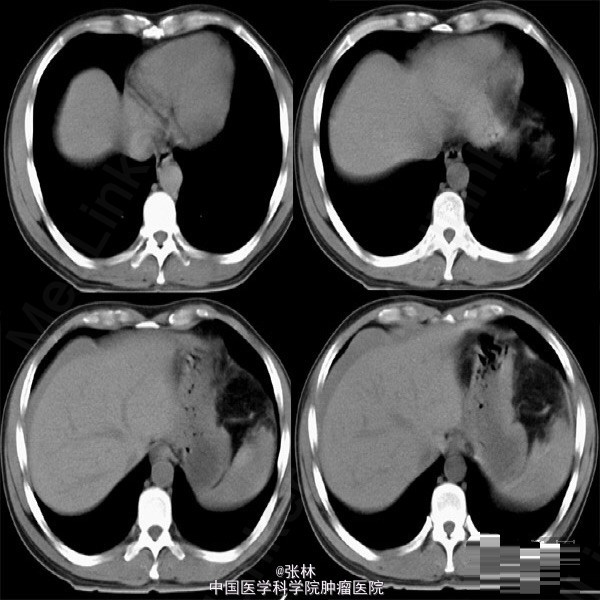

【病史临床】患者,男性,44岁,上腹外伤,疼痛伴呕吐2小时之主诉来诊。CT表现:肝脏周围积液征象,脾脏形态不规则,脾周可见略高密度影。 结果:手术记录如下:(剖腹探查)取上腹正中切口,探查见腹盆腔有较多的积血和血凝块,脾脏表面凹凸不平,肝、脾周有积血。收除腹盆腔积血约1000ML。仔细探查于脾上极脏面可见一深约2cm,长约4cm裂口,时有出血。 最后诊断:外伤性脾破裂。